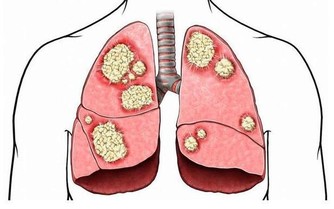

揉腹不但可調理脾胃、防病,

而且對許多慢性病如糖尿病、腎炎、高血壓、冠心病、肺心病等,都有輔助治療作用。